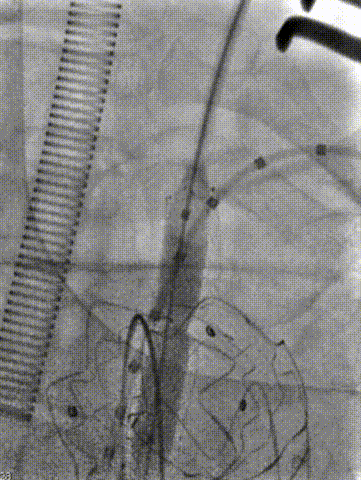

根据术前CT和造影的测量结果,选择PTBS3430180的锥形覆膜支架。在充分降压后,将覆膜区的近端定位在无名动脉后方,逐步释放覆膜支架。释放三节后,再次造影确认覆膜区位置定位良好,随后完成覆膜区全程释放,确保支架位置准确,为后续操作奠定基础。

★ 左侧颈总动脉重建

从预先切开好的左侧颈总动脉穿刺送入6f动脉鞘,将鞘头顶在覆膜支架上,使用asahi treasure 12导丝顺利突破覆膜区。